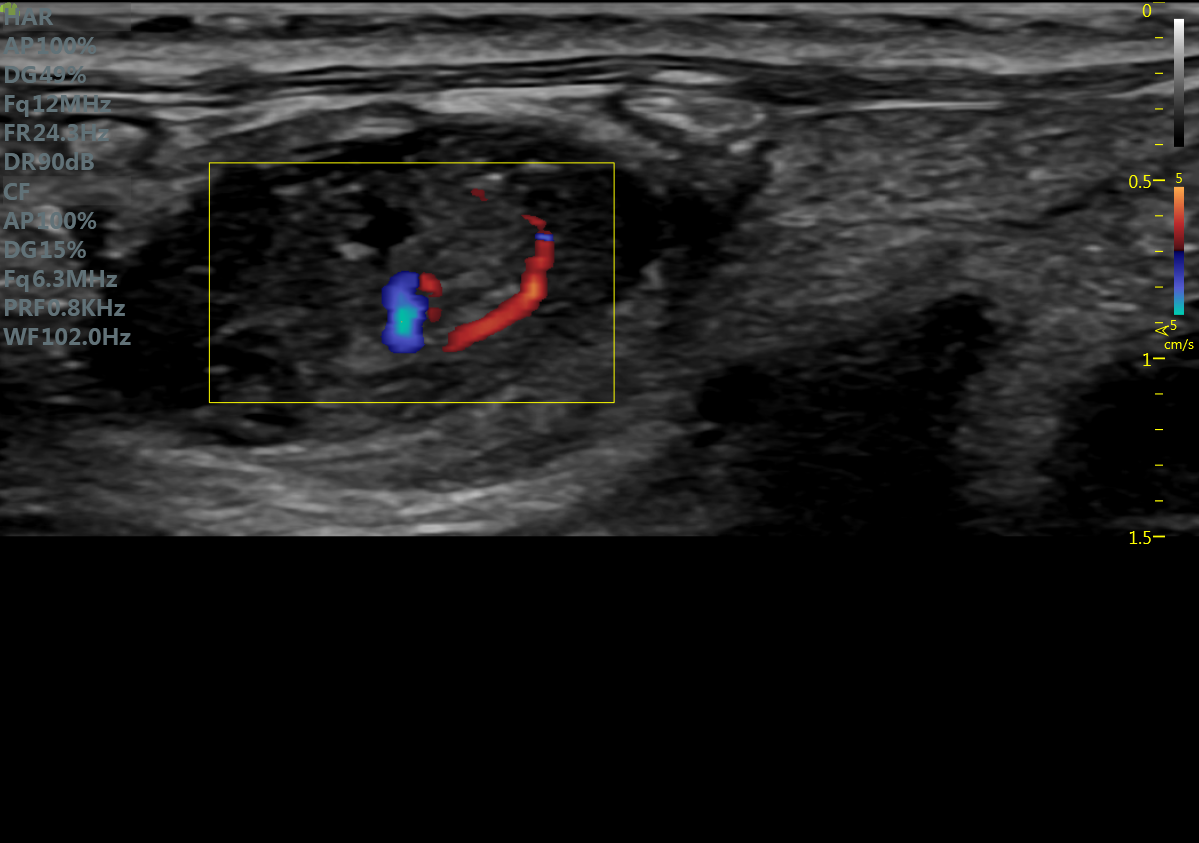

小鼠主动脉弓 小鼠肾脏血流

大鼠胎鼠心脏血流 大鼠心尖四腔